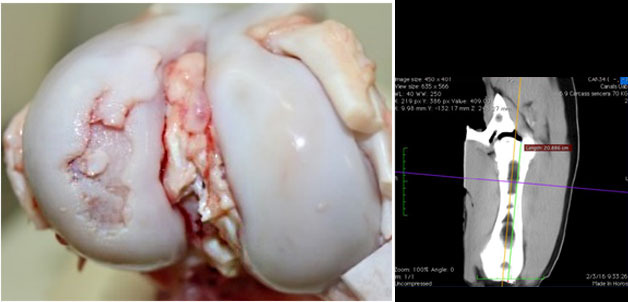

L'osteocondrosi (OC) è una condizione degenerativa e non infettiva delle articolazioni che ha una componente ereditaria. La patogenesi inizia con la condronecrosi ischemica che progredisce verso un'ossificazione anomala e possibili fratture della cartilagine articolare. Si potrebbe ritenere che vi sia un'opportunità di miglioramento nella causa iniziale (80% di prevalenza tra 8 e 12 settimane di età) o in progressione (con recupero del 60-70% a 25 settimane di età). Tuttavia, l'eziologia non è chiara (Olstad et al., 2015) e potrebbe includere traumatismi o fragilità del collagene (Laverty and Girard, 2013; Finnøy et al., 2017). Inoltre, la selezione genetica dovrebbe essere applicata per ridurre la prevalenza della OC, anche se inizialmente potrebbe essere difficile, poiché il potenziale di crescita in carnosità è geneticamente associato alla OC (Aasmundstad et al., 2013). D'altra parte, altri fattori che potrebbero influenzare la progressione della malattia sono poco conosciuti.